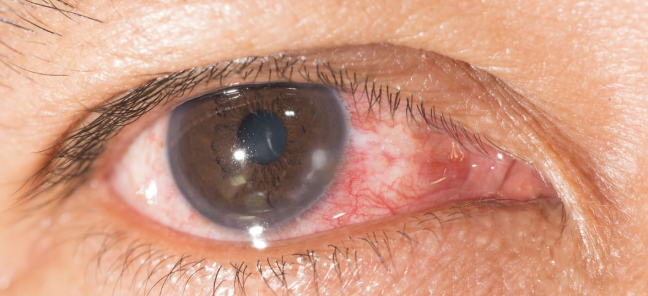

Conjunctivitis

Episcleritis

Abnormal Findings of 6. Inspect bulbar conjunctiva and sclera

Keratitis

One of the 6 Corneal Abnormalities

Inflammation of the cornea, which can be infectious (bacterial, viral, fungal) or non-infectious (due to trauma, dry eyes, or improper use of contact lenses)

Accompanied by eye redness, pain, decreased vision, discharge, and photophobia